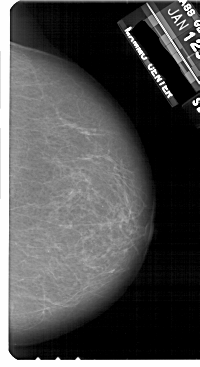

A_1812_1.LEFT_CC

LEFT_CC LINES 5416 PIXELS_PER_LINE 2716 BITS_PER_PIXEL 12 RESOLUTION 43.5 OVERLAY